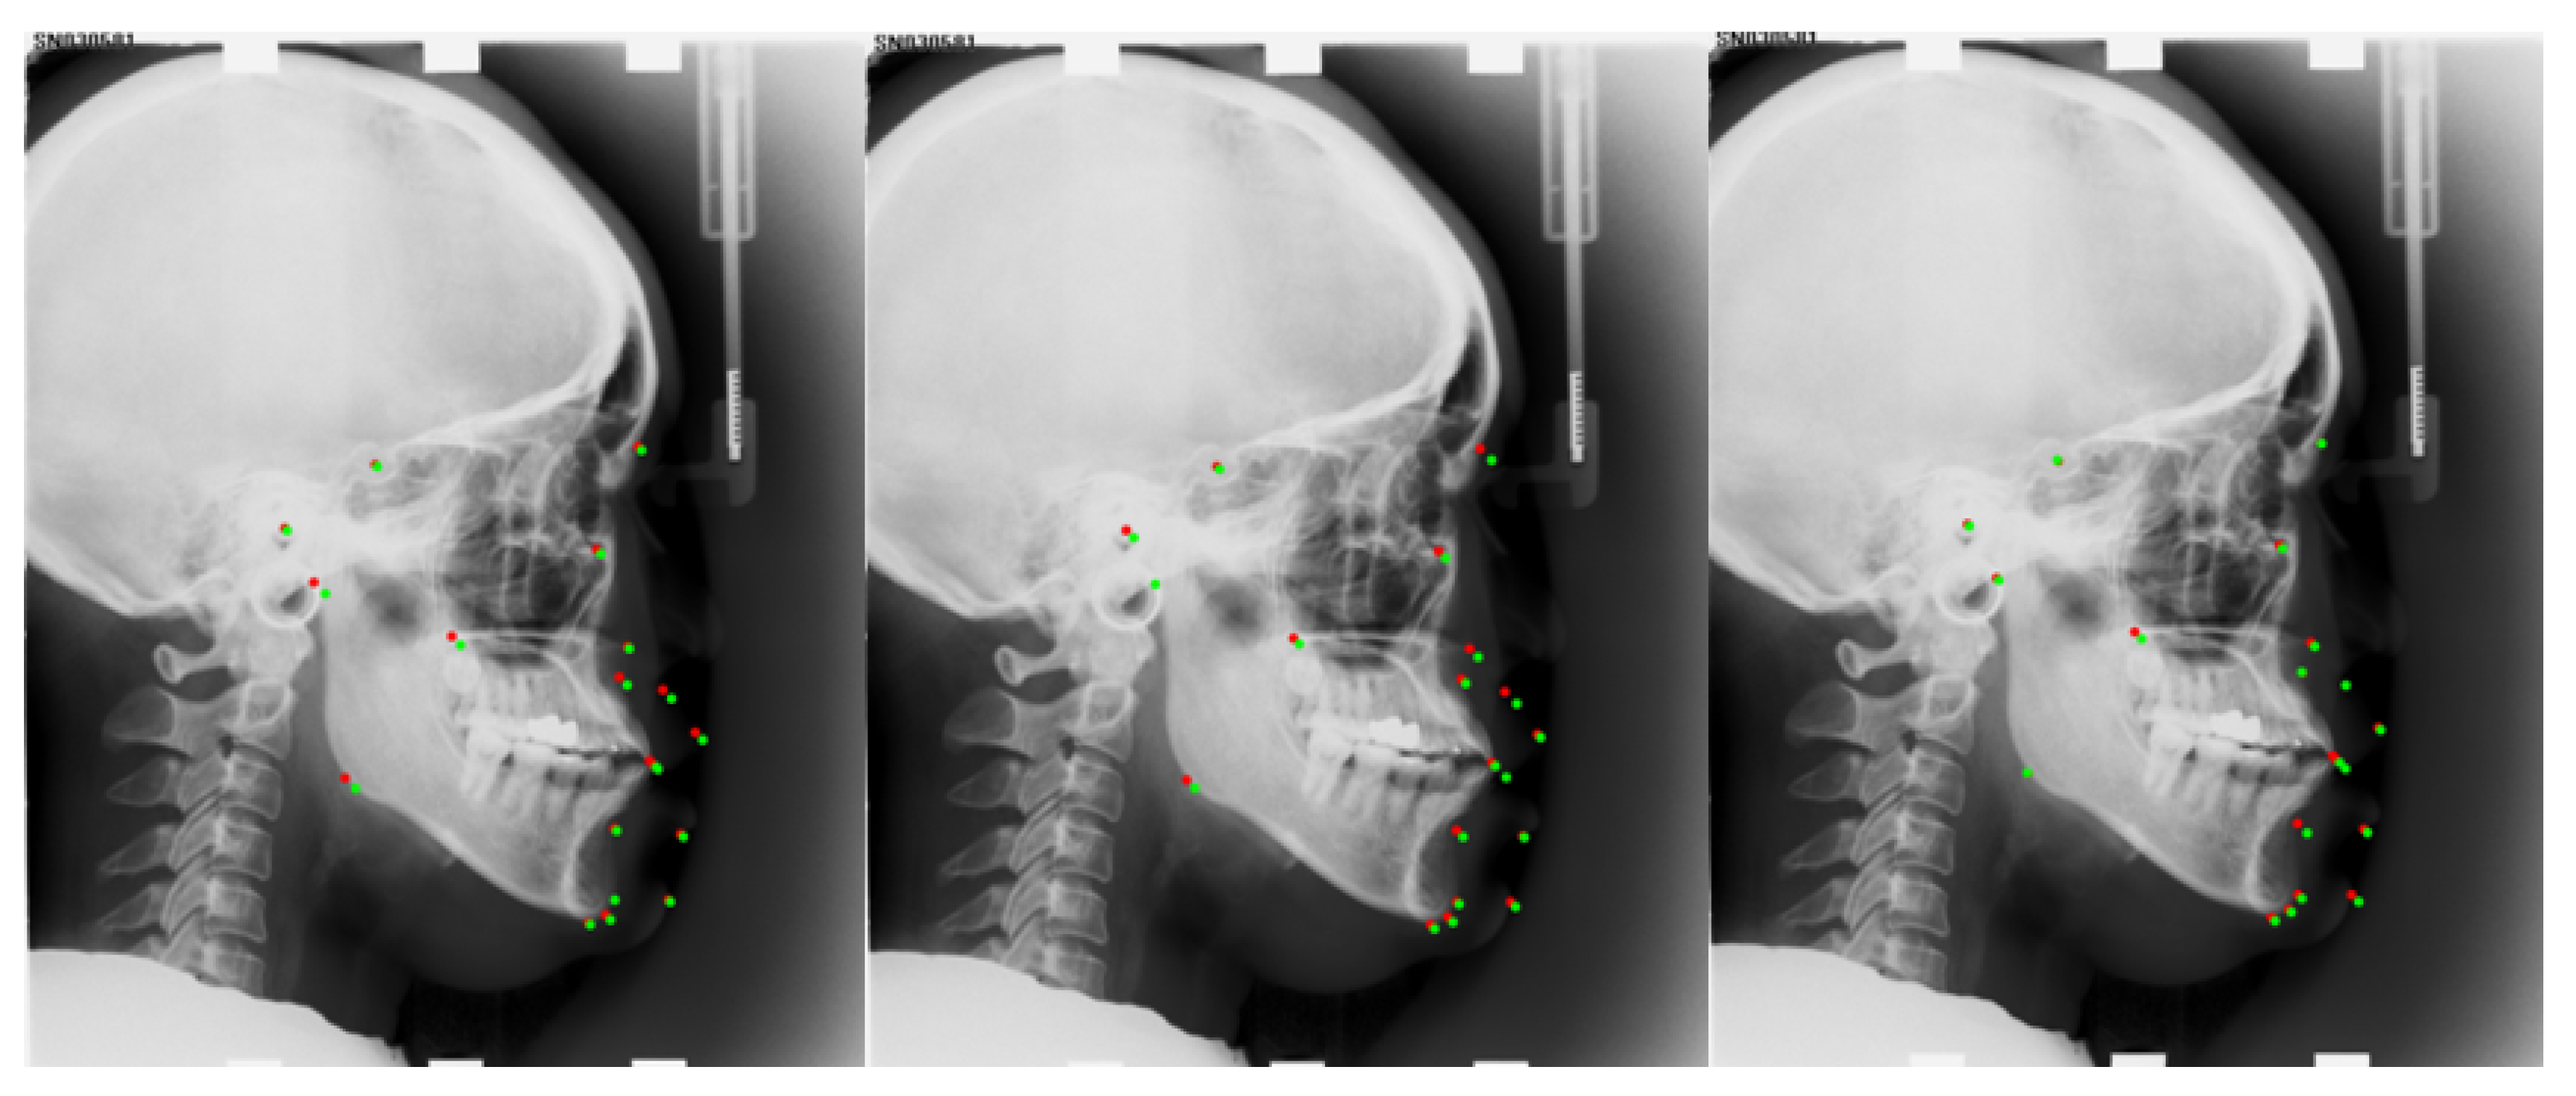

| Anatomical Name | Sella | Nasion | Orbitale | Porion | Subspinale | Supramentale | Pogonion | Menton | Gnathion | Gonion |

| Number | L11 | L12 | L13 | L14 | L15 | L16 | L17 | L18 | L19 | |

| Anatomical Name | Lower incisal incision | Upper incisal incision | Upper lip | Lower lip | Subnasale | Soft tissue pogonion | Posterior nasal spine | Anterior nasal spine | Articulate |